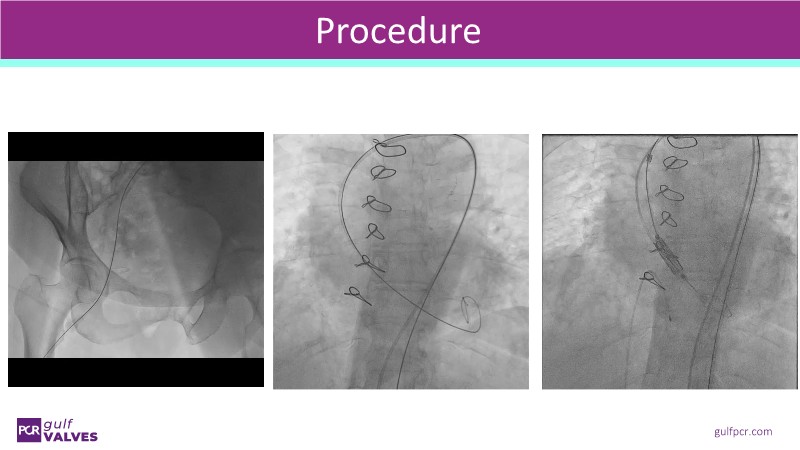

Join this comprehensive session to explore the Myval transcatheter heart valve series, featuring the latest clinical updates from two large randomized controlled trials—Landmark and Compare TAVI. Learn from real-world experiences, including recorded cases, and understand how these innovations translate to complex patient demographics in daily TAVI practice.